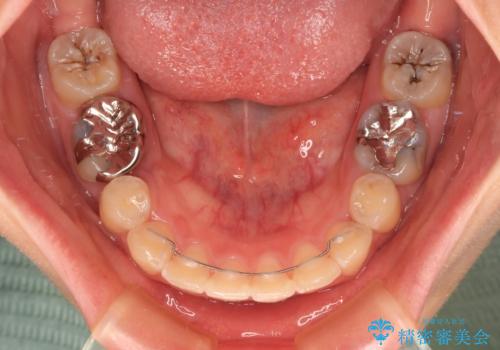

下顎は過剰歯が埋伏しており、それが原因となってスペースが閉じなかったため、途中で抜歯して速やかに仕上げました。